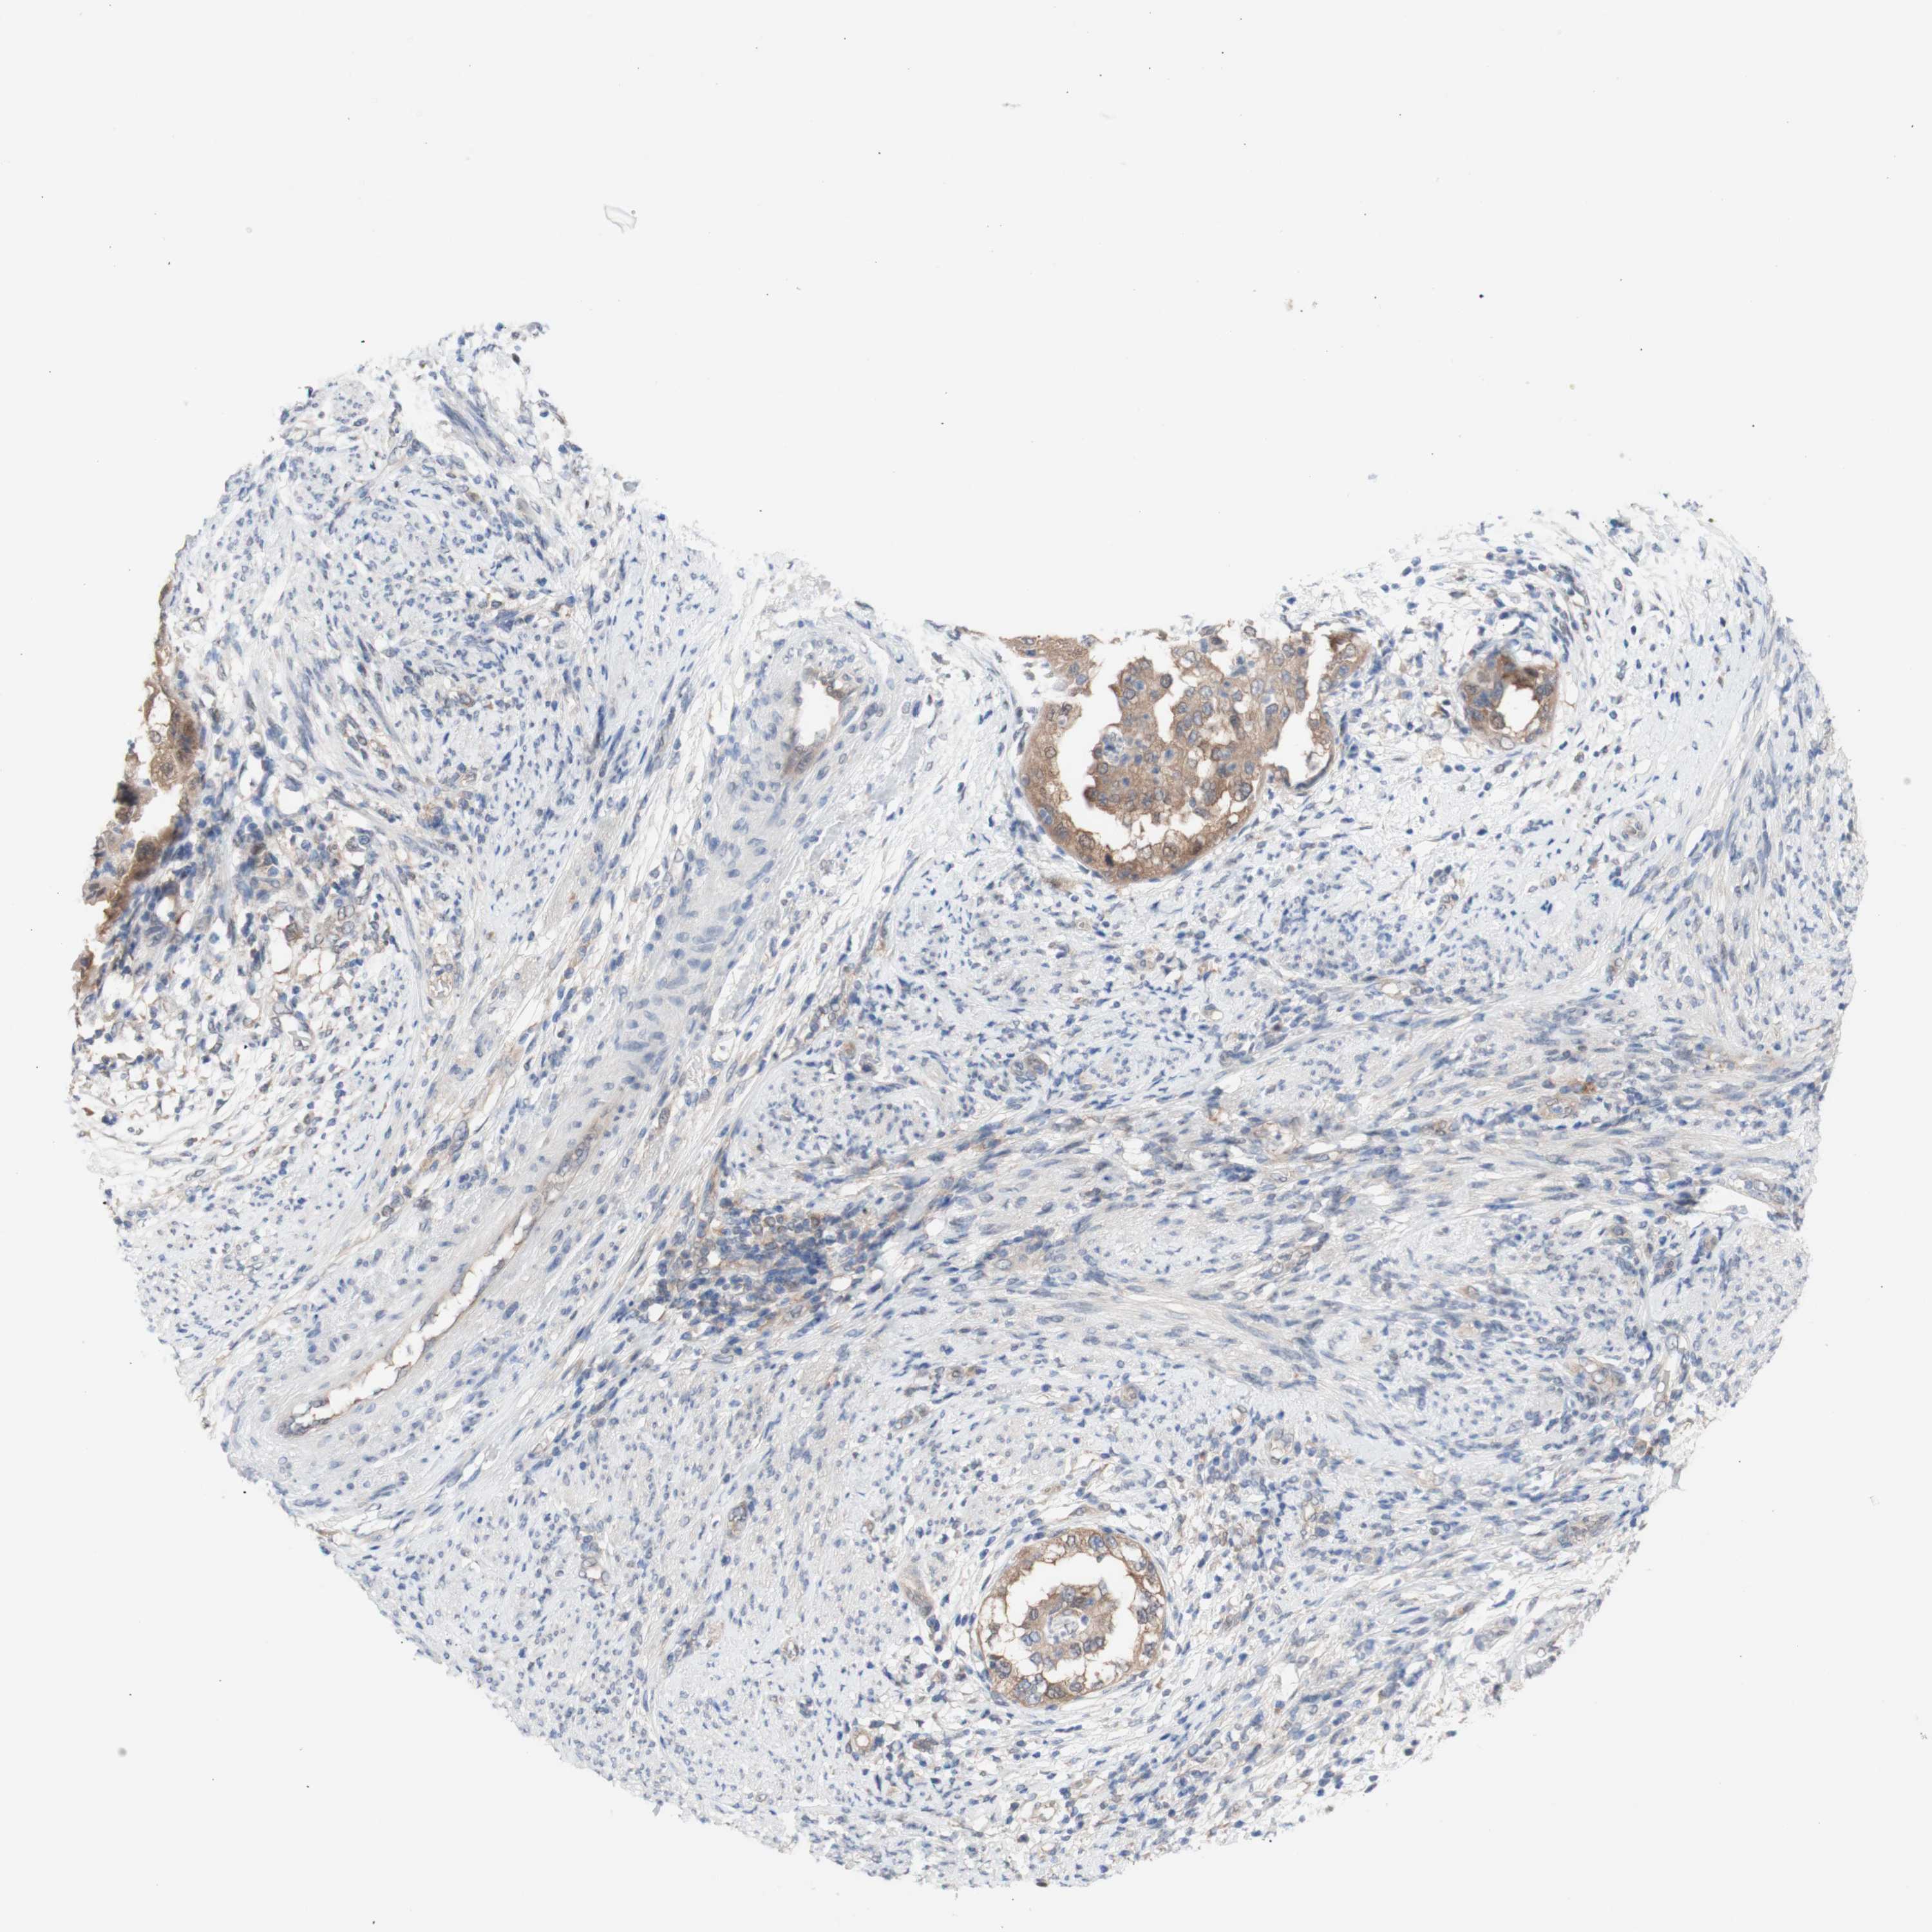

ENDOMETRIAL CANCER - Protein expressioni

A mouse-over function shows sample information and annotation data. Click on an image to view it in a full screen mode. Samples can be filtered based on level of antibody staining by selecting one or several of the following categories: high, medium, low and not detected. The assay and annotation is described here.

Note that samples used for immunohistochemistry by the Human Protein Atlas do not correspond to samples in the TCGA dataset.

Antibody stainingi

Antibody staining in the annotated cell types in the current human tissue is reported as not detected, low, medium, or high, based on conventional immunohistochemistry profiling in selected tissues. This score is based on the combination of the staining intensity and fraction of stained cells.

Each image is clickable and will lead to virtual microscopy that enables deeper exploration of all samples and also displays staining intensity scores, fraction scores and subcellular localization as well as patient and tissue information for each sample.

Antibody HPA005525

Antibody HPA064708

Antibody CAB012459

Staining

High

Medium

Low

Not detected

Intensity

Strong

Moderate

Weak

Negative

Quantity

>75%

75%-25%

<25%

None

Location

Nuclear

Cytoplasmic/membranous

Cytoplasmic/membranous,nuclear

Adenocarcinoma, NOS

Neoplasm, malignant, NOS

Adenocarcinoma, metastatic, NOS